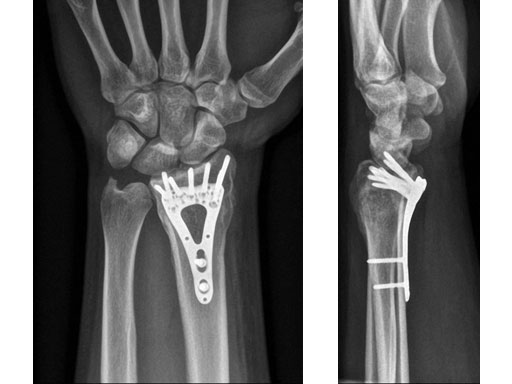

22-year-old male fell off a horse while playing polo.

Case provided by Ladislav Nagy, Zrich, CH

Fig 4ab X-rays 3 months postoperatively.